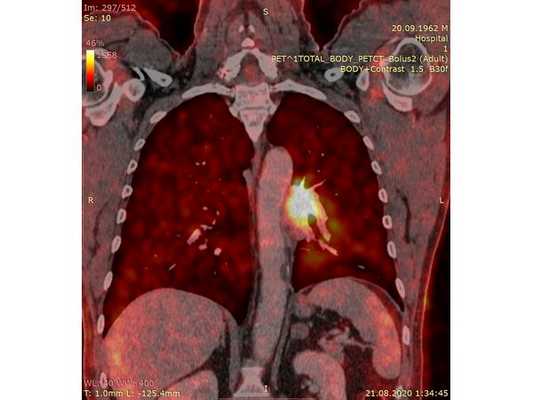

Чтобы провести первичное стадирование опухоли, пациенту проведена позитронно-эмиссионная томография в сочетании с компьютерной томографией (ПЭТ-КТ). По данным исследования, выявлена метаболически активная опухоль в корне левого лёгкого с бугристыми контурами размерами 41 х 43 мм. В толще опухоли проходят нижнедолевой бронх и бронх 6-го сегмента левого лёгкого, просветы бронхов значительно сужены. Нижняя доля левого лёгкого уменьшена в размерах за счёт того, что сегменты 6, 9 и 10 субтотально (частично) инфильтрированы и безвоздушны. Лимфатические узлы корня лёгкого и средостения не увеличены в размерах и не накапливают радиофармпрепарат (РФП), который был введён пациенту перед обследованием внутривенно. Других очаговых образований и очагов гиперметаболизма в организме не обнаружено.

При этом отмечено, что опухоль распространяется в средостение по нижней стенке левого главного бронха и широко прилежит к нижнегрудному отделу аорты (по заключению специалиста ПЭТ-КТ — имеется инвазия опухоли в ткани средостения и возможное врастание в стенку аорты). При самостоятельном пересмотре изображений отмечено, что "опухолевая" ткань, которая распространяется по нижней стенке левого главного бронха в средостение, не накапливает РФП (т. е. не является злокачественной), а стенка аорты в области "инвазии" опухоли имеет ровный чёткий контур и адвентициальную границу, что также свидетельствует об отсутствии онкологического процесса в этой области.